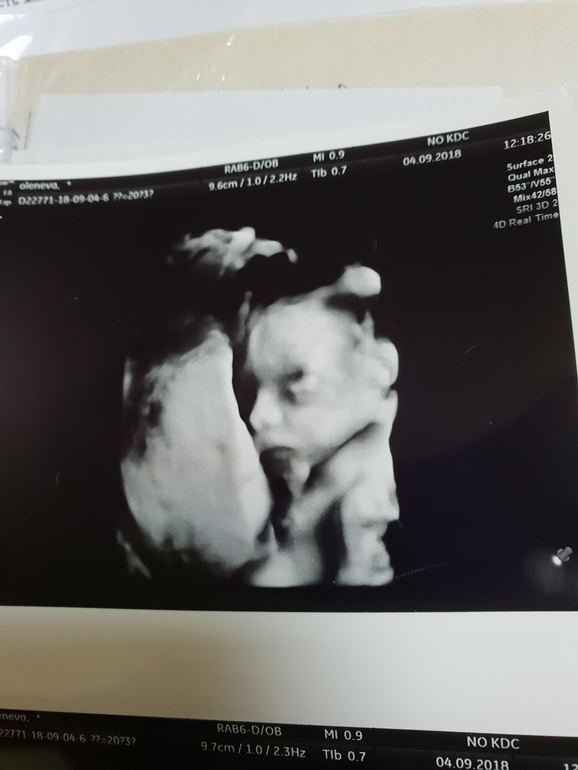

Ну и вот она наша красотка

И результаты УЗИ: